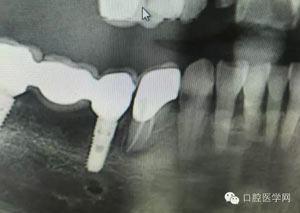

病例2:364647中齲的樹脂充填,現在樹脂的充填材料非常之多,有些時候,我們感覺有了好的材料我們就可以做出好的修復,可是這是在我們有扎實的基本功的基礎上的,我們可以沒有那么好的樹脂,那么多的顏色選擇,修復的那么的逼真,但是我們至少要恢復患者牙齒的功能,將腐質去除干凈,薄壁弱尖消除掉,選擇好適應癥,給患者以盡可能好的修復。

30.jpg

31.jpg

32.jpg

33.jpg

34.jpg

35.jpg

36.jpg